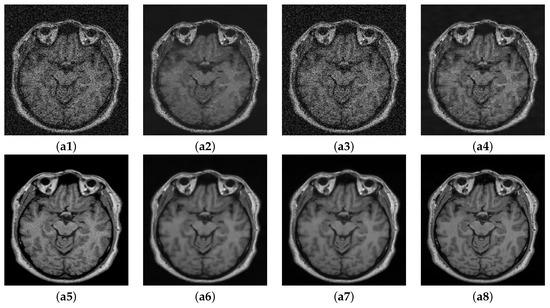

In this section, we summarize the discussion of our results. The results of Experiment I are shown in Figure 5, Figure 6 and Figure 7, where the denoising performance of the proposed method is shown in comparison with state-of-the-art denoising methods. In Figure 5, the input images were contaminated using 13% noise. All the images denoised using different approaches suppress noise to some extent; however, NLM [10] removes important structural details in the image and oversmoothes the contents of the denoised image during the restoration. Wavelet-based technique SURE [58] and BM3D [59] preserve the structural details; however, they do not eradicate noise to a reasonable extent. The deep learning methods clearly show better performance compared to the traditional methods, both in removing noise and maintaining the morphology of the image. Both MCDN [24] and FFD-Net [53] effectively remove the noise. Similarly, C M G D N e t also eradicates noise with reasonable preservation of the structural information. The enlarged ROIs are also shown in the figure for careful insight into the denoising performance of all the methods. Figure 6 shows the results of denoising applied on images contaminated with 8% noise. A similar trend can be observed in this case as well where the methods MCDN [24], FFD-Net [53], and C M G D N e t preserve important structures in the denoised images. However, NLM [10] produces over-smoothing effects. The performance was quantitatively evaluated using PSNR, SSIM, and FSIM. BM3D [59] works better compared to NLM and SURE [58]; this claim is also supported by the higher PSNR value in Table 2. The performance of FFD-Net [53] and MCDN is very similar when quantitatively evaluated. However, C M G D N e t performs best among all the techniques evaluated.

Figure 5. Comparison of proposed method with state-of-the-art denoising methods: (a1) Noisy. (a2) NLM [10]. (a3) SURE [58]. (a4) BM3D [59]. (a5) MCDN [24]. (a6) FFD-Net [53]. (a7) C M G D N e t s g . (a8) GT, Corresponding enlarged regions of the denoised images: (b1) Noisy. (b2) NLM [10]. (b3) SURE [58]. (b4) BM3D [59]. (b5) MCDN [24]. (b6) FFD-Net [53]. (b7) C M G D N e t s g . (b8) GT.